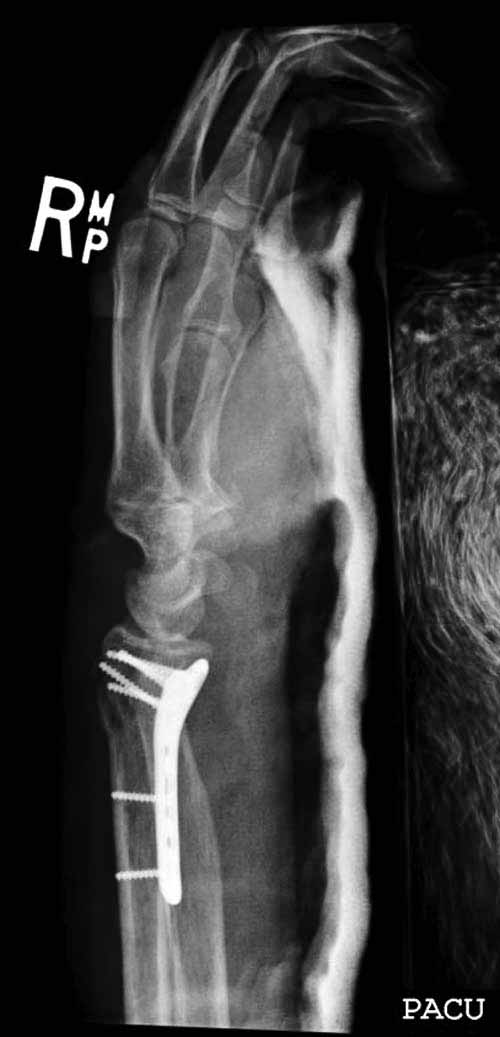

Сегодня все компании: Synthes, Stryker, Zimmer, Acumed, TriMed и т.д. имеют пластины для фиксации дистального перелома лучевой кости. На снимке метод фиксации дистальных переломов, справа Stryker, а слева пластина Synthes,

женщина 58 лет, политравма.